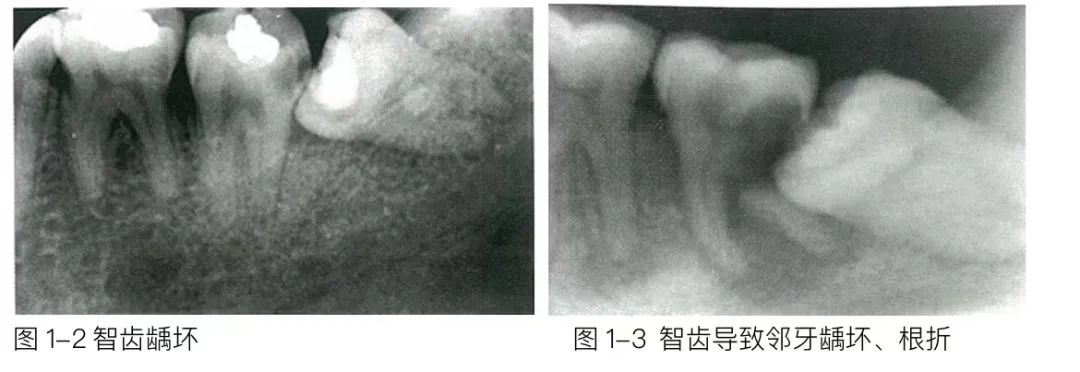

这种智齿无论是斜的还是躺着的,都走上了“细菌养殖业”的歪路,同样会让细菌腐蚀旁边的牙齿。

4.发生大面积龋坏、牙髓炎或根尖周炎的智齿

对于这样的智齿,均建议拔除。因为能烂成这样,说明了清洁它的难度或你对它的重视程度,且非拔除治疗后重新发生龋坏或根尖周炎的风险更高。